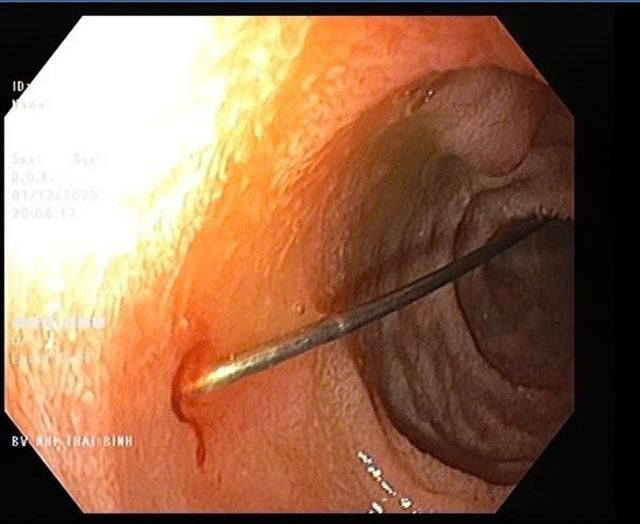

Sau khi thăm khám, trẻ được chẩn đoán dị vật đường tiêu hóa và chỉ định nhập viện vào Khoa Tiêu hóa để theo dõi, hội chẩn và xử trí cấp cứu. Hình ảnh nội soi quan sát thấy niêm mạc thực quản và dạ dày của trẻ không viêm loét; tại hành tá tràng D1-D2 phát hiện dị vật kim may dài 4cm, một đầu nhọn cắm vào thành tá tràng, một đầu nhựa tròn hình cúc đang nằm trong lòng ruột.

Qua nội soi phát hiện cây kim dài 4cm. Ảnh: Bệnh viện cung cấp.